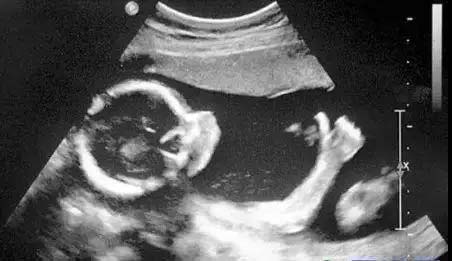

1,孕妈妈们对B超不会陌生。b超是通过超声波和成像技术形成的影像。,来判断正常组织和病灶的性质。B超和之前提到的三项检查有着较大的区别,但是因为B超机的探头掌握在B超医生的手上,指哪打哪,因此相对更依赖于检查医生的经验。,,

2,不同部位的b超检查项目,注意事项也是不同的。如检查腹部b超最好选择上午,因为上午腹腔气体少,干扰小,更利于观察诊断。在做妇科检查前,一定要避开经期。